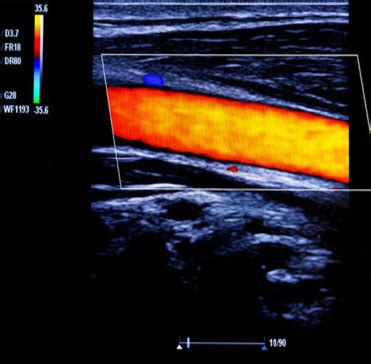

Now, let’s talk about the star of the show: how Doppler ultrasound specifically helps us spot Deep Vein Thrombosis (DVT). DVT occurs when a blood clot, usually in a deep vein of the legs, blocks blood flow. This is serious business, as the clot can break off and travel to the lungs, causing a pulmonary embolism (PE), which is a life-threatening condition. Doppler ultrasound is the gold standard for diagnosing DVT because it can directly visualize these clots and, crucially, assess the impact on blood flow. The procedure typically involves a trained sonographer applying a gel to your skin over the suspected area (usually the legs) and then moving a transducer, a handheld device, over the skin. This transducer emits high-frequency sound waves. As these waves travel through your body, they bounce off various tissues and structures, including your blood vessels and the red blood cells within them. The machine listens to the returning echoes. In areas without a clot, the sound waves will reflect off the moving blood cells predictably, showing a normal flow pattern. However, when a clot is present, it can partially or completely block the vein. This blockage will alter the sound wave reflections in several ways:

1. Direct Visualization of the Clot: In many cases, the clot itself can be seen as an echogenic (bright) material within the vein, obstructing the normal lumen (the open space where blood flows). The sonographer looks for a lack of compressibility of the vein; a healthy vein will flatten when gentle pressure is applied by the transducer, but a vein filled with a clot will remain rounded.

2. Altered Blood Flow Patterns: This is where the ‘Doppler’ part really shines. The machine detects changes in the frequency of the returning sound waves. If blood flow is reduced or absent in a segment of the vein due to a clot, the Doppler signals will be weaker or absent altogether. The sonographer will assess ‘phasicity’ (the normal rhythmic changes in blood flow related to breathing) and ‘compressibility’ of the veins. A clot disrupts these normal flow characteristics.